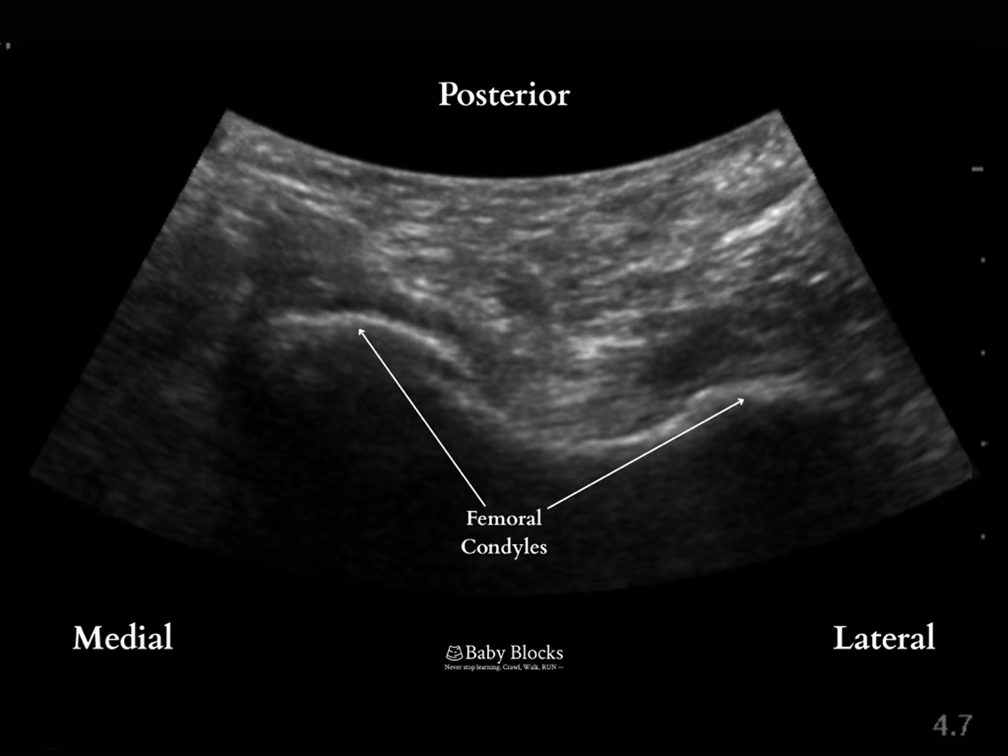

· Scanning is performed along the femur to find the posterior view of the femoral condyles.

At the level of the femoral condyles